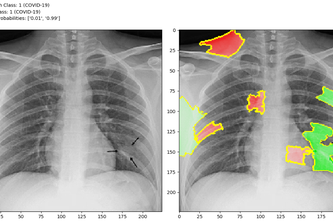

An extensible, open source and explainable deep CNN model for redicting the presence of COVID-19 in chest x-rays.